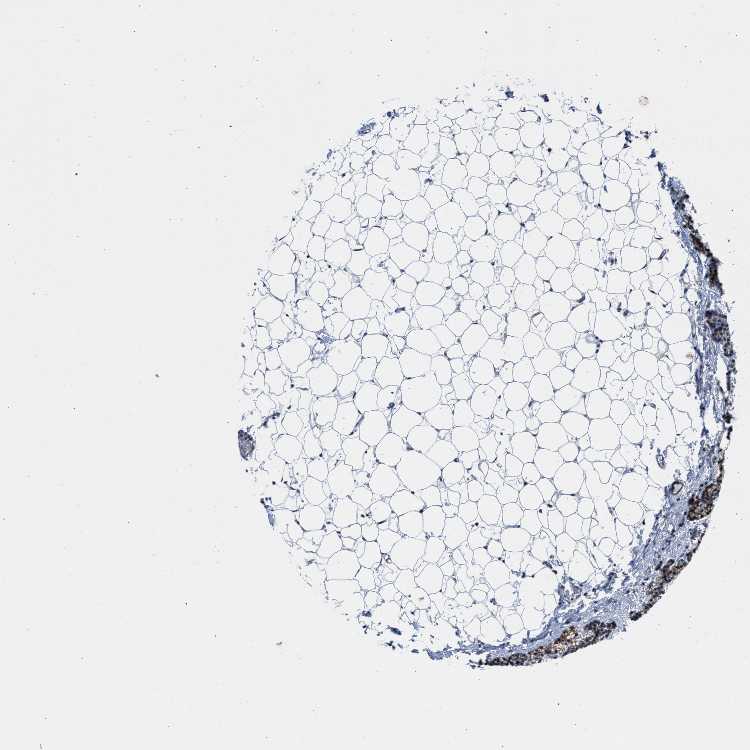

TISSUE PRIMARY DATA PARATHYROID GLAND Show tissue menu

PARATHYROID GLAND - Antibody stainingi

Antibody staining in the annotated cell types in the current human tissue is reported as not detected, low, medium, or high, based on conventional immunohistochemistry profiling in selected tissues. This score is based on the combination of the staining intensity and fraction of stained cells.

Each image is clickable and will lead to virtual microscopy that enables deeper exploration of all samples and also displays staining intensity scores, fraction scores and subcellular localization as well as patient and tissue information for each sample.

Antibody HPA021590

Glandular cells High